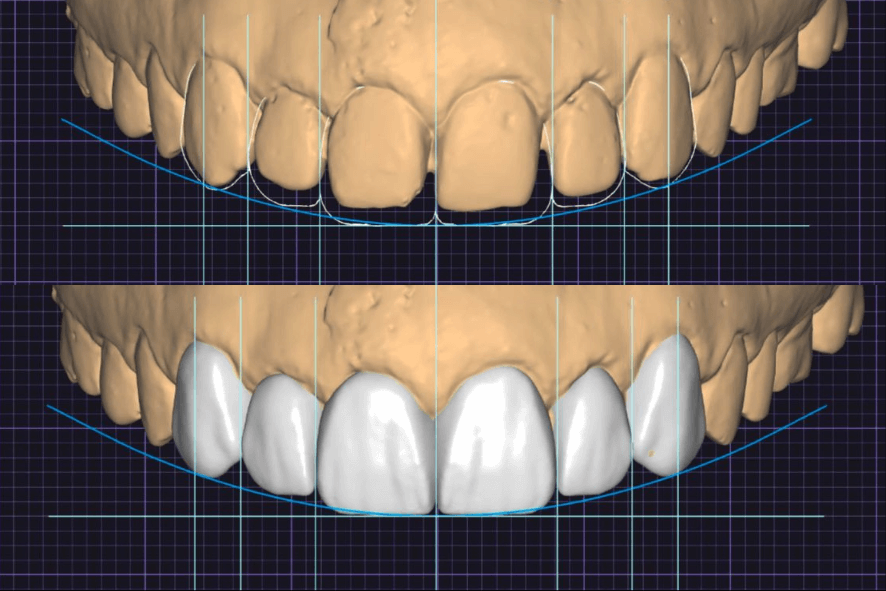

Lentes de Porcelana e Facetas de Resina

- Lentes de Porcelana: são lâminas ultrafinas de porcelana, feitas em laboratório, de altíssima qualidade, brilho e durabilidade.

- Facetas de Resina: são utilizadas resinas compostas de alto padrão aplicadas diretamente no dente pelo dentista, com técnica e habilidade.

Lentes de porcelana

1) Lente de contato dental x faceta de resina: qual a diferença? Ambos precisam desgastar o dente?

Nas lentes de porcelana, é mais comum indicar um desgaste mínimo e controlado para corrigir volume, posição e adaptação. Já nas facetas de resina, muitas vezes realizamos mais um acréscimo de material do que desgaste, e quando o desgaste é necessário, ele é bem sutil.

É importante lembrar que a espessura final depende sempre do tamanho e da posição dos dentes, tanto nas lentes quanto nas facetas de resina. Na Santé seguimos o princípio da mínima intervenção: só desgastamos quando necessário e na medida exata, após planejamento digital (fotos, escaneamento 3D e mock-up). Quando o caso permite, fazemos abordagens sem desgaste (“no-prep”).

4) Quem pode fazer lentes de porcelana? Precisa alinhar ou clarear antes de fazer lentes de contato no dente?

As lentes são indicadas para remover manchas, melhorar cor, melhorar formato, corrigir pequenas diferenças de alinhamento dos dentes e fechamento de espaços (diastemas). Em alguns casos, clarear ou alinhar antes são obrigatórios para melhorar o resultado e a longevidade das lentes de contato dentais.